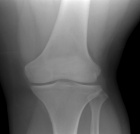

25 year old woman with a six month history of left knee pain

Zoom image: Radiological image Radiological image.